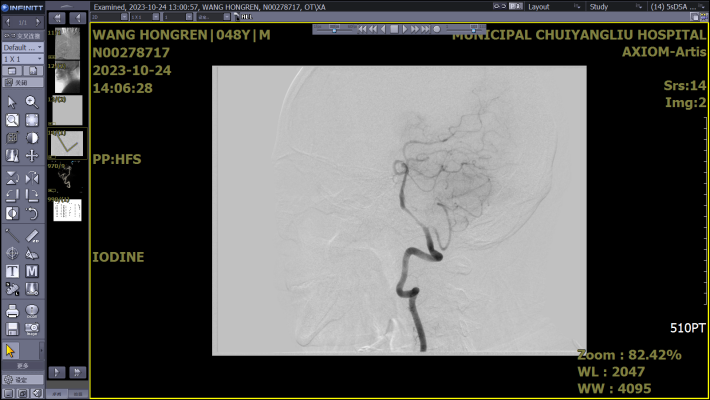

五、数字减影血管造影(DSA)

是通过电子计算机进行辅助成像的血管造影方法,这项技术所显示的图像更清晰和直观,一些精细的血管结构亦能显示出来,可清楚地显示动脉管腔狭窄/闭塞、侧支循环建立情况、动脉瘤、血管畸形等,可为患者是否需要进行后续治疗(如血管内支架植入术、动脉瘤填塞术等)提供可靠的评估依据。优点是此项检查较为精准全面,是颅内外血管评估的金标准,缺点是价格昂贵,属于有创检查,基层医院难以开展,故临床上不能作为首选的常规检查手段,需要遵从专科医生的建议。